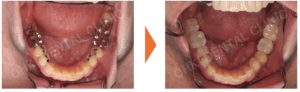

【症例紹介】重度歯周病からのフルマウス(全顎)治療|インプラントとブリッジによる審美・機能回復

1年で手に入れる“一生モノ”の笑顔と噛み合わせ 「歯ぐきが下がって、見た目が悪くなってきた」「前歯が伸びてきて唇に当たる...